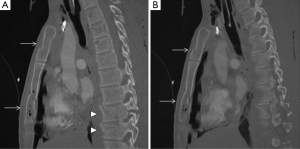

A rare clinical emergency so-called “deep tissue injury syndrome (DTI)” has been previously reported, characterized by a severe pressure ulcer necrotic tissue mass under intact skin (39). This unusual entity affects unconscious patients lying down in the same position after a long period of time, where thoracic wall muscles could be damaged. DTI can be identified using US (40), CT (41) and MRI (42). Soft-tissue swelling with myonecrosis is the hallmark of this pathology (Figures 15,16). It often requires surgical interventions and endangers the life of patients with motosensory impairments (43). Therefore, a delayed diagnosis must be avoided.